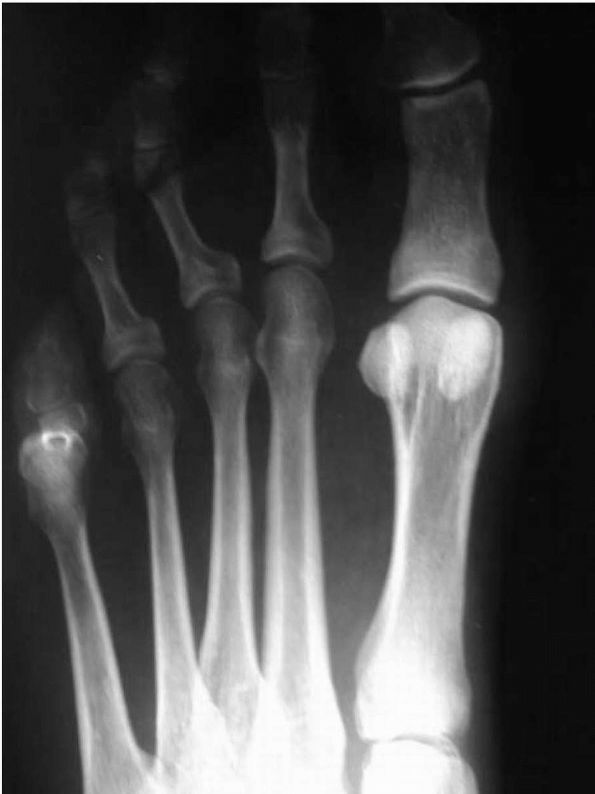

![]() |

FIGURE 21-9. (A and B)

First metatarsophalangeal joint in a patient with hallux rigidus. Note the increased bulk of the joint and marked osteophyte formation. (C) Lateral radiograph of a patient with hallux rigidus, with a large dorsal osteophyte that mechanically blocks dorsiflexion of the proximal phalanx. |

characteristic, demonstrating degenerative arthritis of the

metatarsophalangeal joint on the anteroposterior (AP) view. Besides the

narrowing of the joint, significant osteophyte formation is often

present along the lateral aspect of the joint. Medially, there rarely

is significant osteophyte formation. On the lateral view, there is a

dorsal osteophyte of varying degrees. Occasionally, there is an

osteophyte on the dorsal aspect of the proximal phalanx as well. In

advanced stages, the entire joint space may be compromised. This